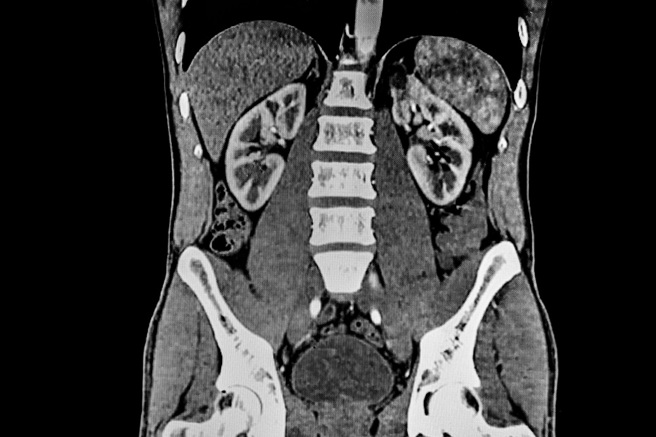

经过电脑断层扫描的结果显示,男子的肠道堆了大量的硬币与磁铁,造成肠阻塞,于是紧急安排手术,手术过程中,医师发现磁体和硬币已经将小肠的不同环道吸在一起,磁力导致它们黏附,肠壁也因此遭到侵蚀。

最终在医师「开肠剖肚」之下,成功取出39枚硬币和37块磁铁,并透过X光检查,确认肠胃中所有异物已经清除乾净,手术后男子恢復状况良好,住院观察7天后便可出院,只是后续仍需接受精神疾病的治疗;而医生则透过这起案例提醒大眾,吞食异物可能致死,千万不要拿自己的生命开玩笑。